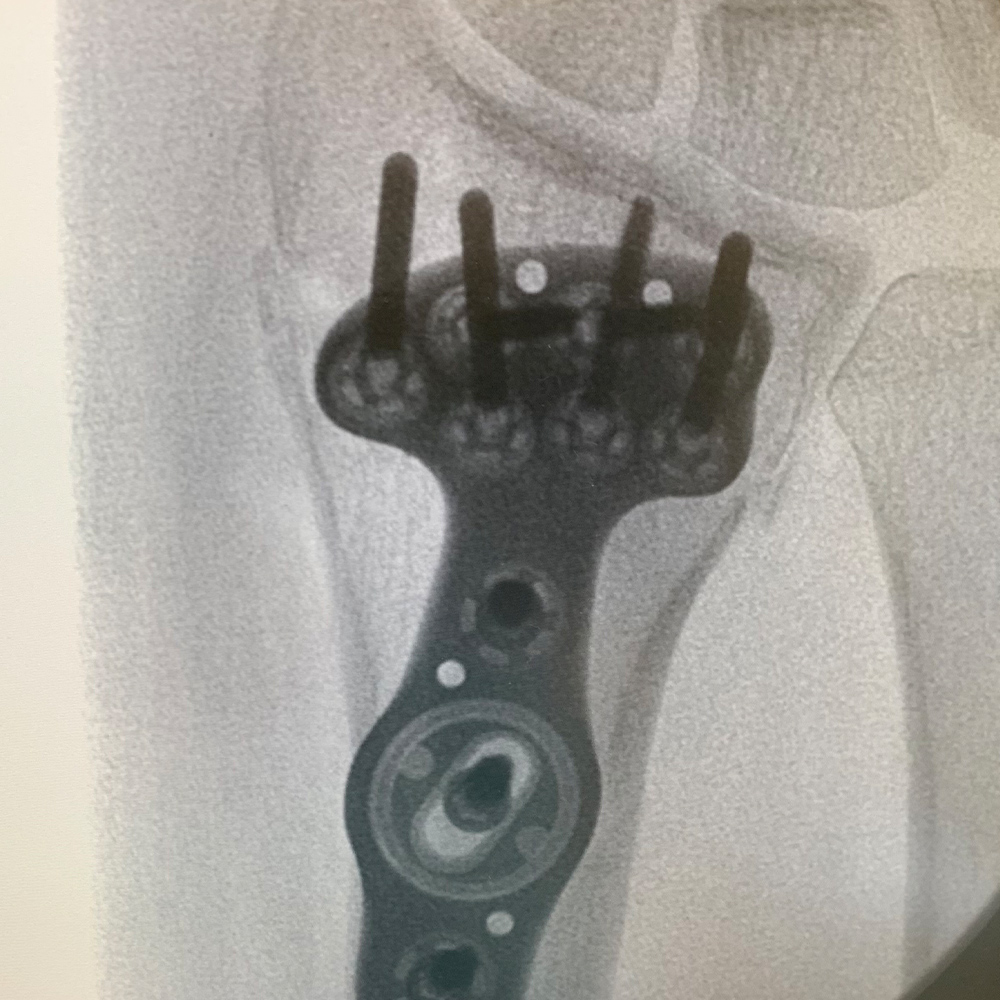

Proximal Humerus Solutions

Plating System

- 40° Polyaxial locking

- Strong & consistent locking at every angle

- Titanium low-profile construct

- Compression before locking

- Locking caps improve fatigue properties and prevent screw back out

- The system allows for precise screw placement independent of the plate position

- Polyaxial drill guides allow for provisional K-wire fixation

- Sutures can be passed before or after osteosynthesis